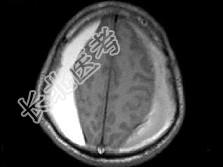

- 单项选择题男,59岁, 半月前与人打架后感头痛头昏,双侧肢体无力, 根据所提供图像,最可能的诊断是 ( )

A、双侧额顶部硬膜下血肿

B、双侧额顶部硬膜外血肿

C、双侧额顶部脑挫裂伤

D、双侧额顶部急性硬膜外血肿

E、双侧额顶部慢性硬膜外血肿